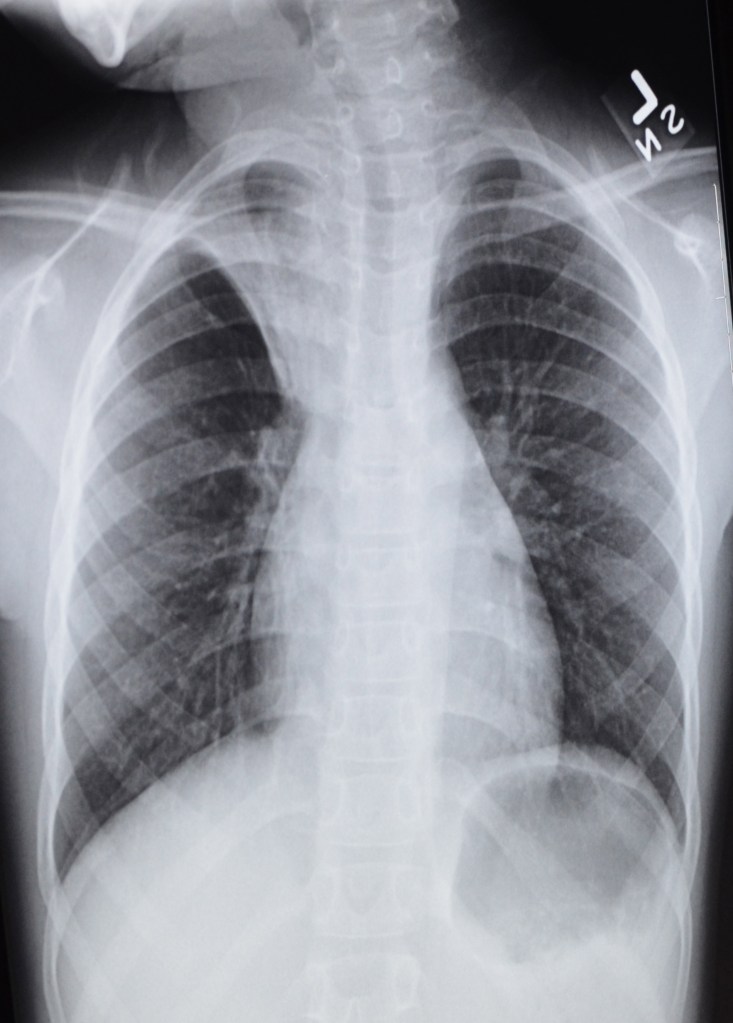

Opportunities to see how much pneumatic lungs and snowy winter trees look alike.